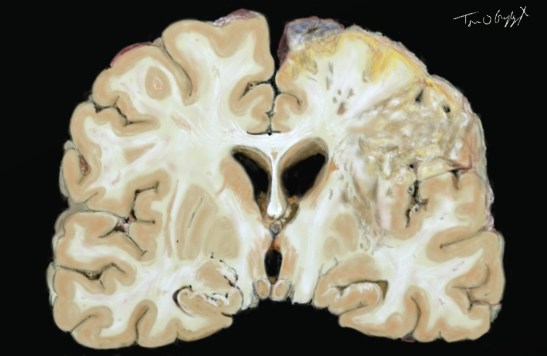

Accident vasculaire cérébral ischémique constitué. ramollissement cérébral pariétal gauche